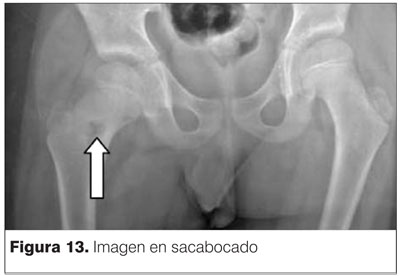

Presenta buena evolución postoperatoria. Al segundo mes se permite la marcha con carga completa. Se solicitan radiografías de control donde se aprecia la imagen en sacabocado generada por el trocar durante la punción tomográfica (figura 13).